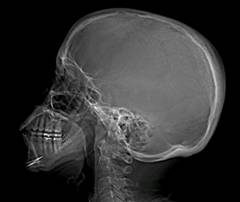

Рентгенография, компьютерная томография и магнитно-резонансная томография черепа Эти исследования помогают оценить состояние головного мозга и костей черепа, обнаружить заболевания, которые стали причиной вторичных нервных тиков.

Рентгеновские снимки черепа делают в разных проекциях.

Компьютерная и магнитно-резонансная томография позволяют получить снимки с послойными срезами или трехмерными изображения внутричерепных структур.